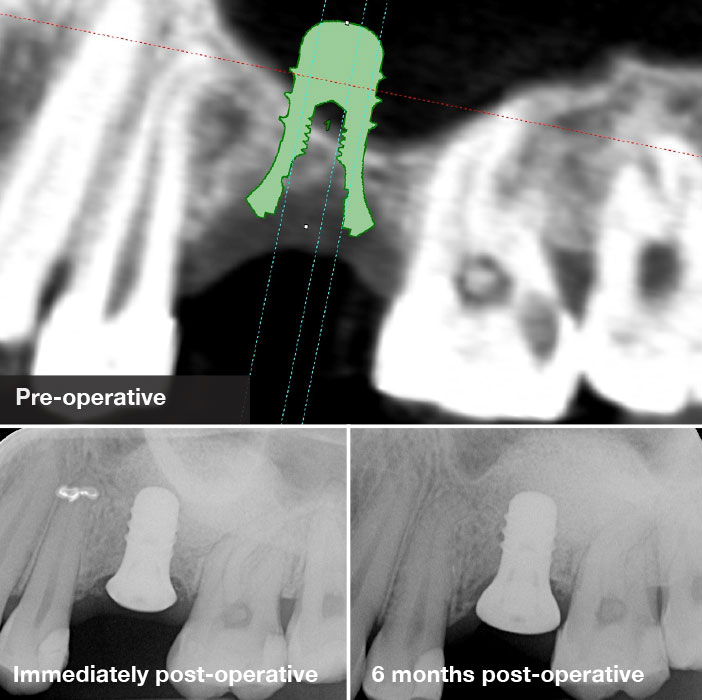

Lateral window sinus floor elevation with simultaneous implant placement

The case above describes implant placement to replace a missing upper left molar. Radiographic assessment revealed a low sloping floor of the maxillary sinus. The sub-antral bone height was 3-5mm. The surgical procedure involved utilising a piezosurgical device to carry out the antrostomy. The elevation of the schneiderian membrane was facilitated by specially designed piezosurgical tips. The grafting material used was a combination of autogenous bone scrapings and xenograft (Bio-Oss). An implant was then placed at the same appointment. Radiographic follow up shows excellent integration of the implant and grafted bone.